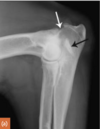

13

Q

A

Avulsed olecranon (fracture)

Where do (typically) olecranon avulsion fractures occur?

In young animals - at the physis.

In mature animals - at the semilunar/trochlear notch (more distally)